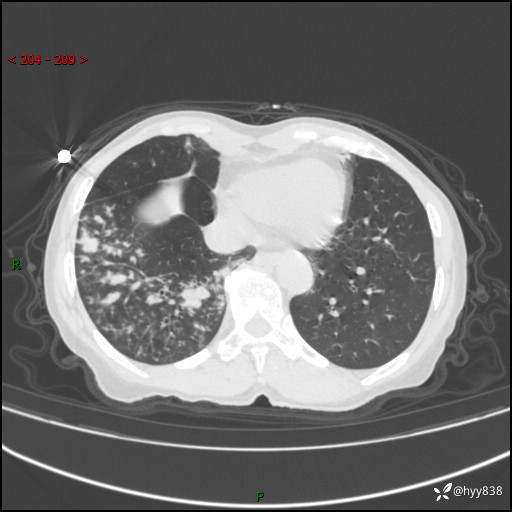

患者性别:男

患者年龄:69岁

简要病史:咳嗽咳痰2月,夜间加重

辅助检查:CT

临床诊断:感染

胸部CT平扫